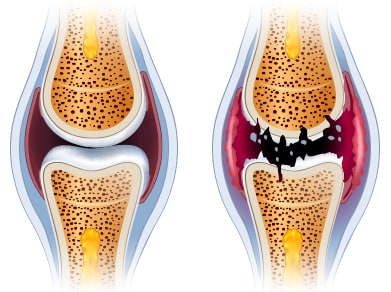

3. 고관절 통증 증상 - 퇴행성 고관절염

연골이 닳으면서 관절 사이 간격이 줄어들고 통증과 강직이 나타납니다. 초기에는 소염진통제나 연골 보호제, 휴식과 적절한 운동으로 경과를 관찰하며 보존적 치료를 시도합니다. 보존적 치료로 증상이 호전되지 않거나 기능 저하가 심하면 수술적 치료를 고려할 수 있습니다.

5. 퇴행성 관절염

연골 보호층이 닳아 없어지면 뼈와 인대에 손상이 발생하고 염증과 만성 통증이 생깁니다. 연골 손상으로 인한 통증은 회복이 더디므로 조기 관리가 필요합니다.